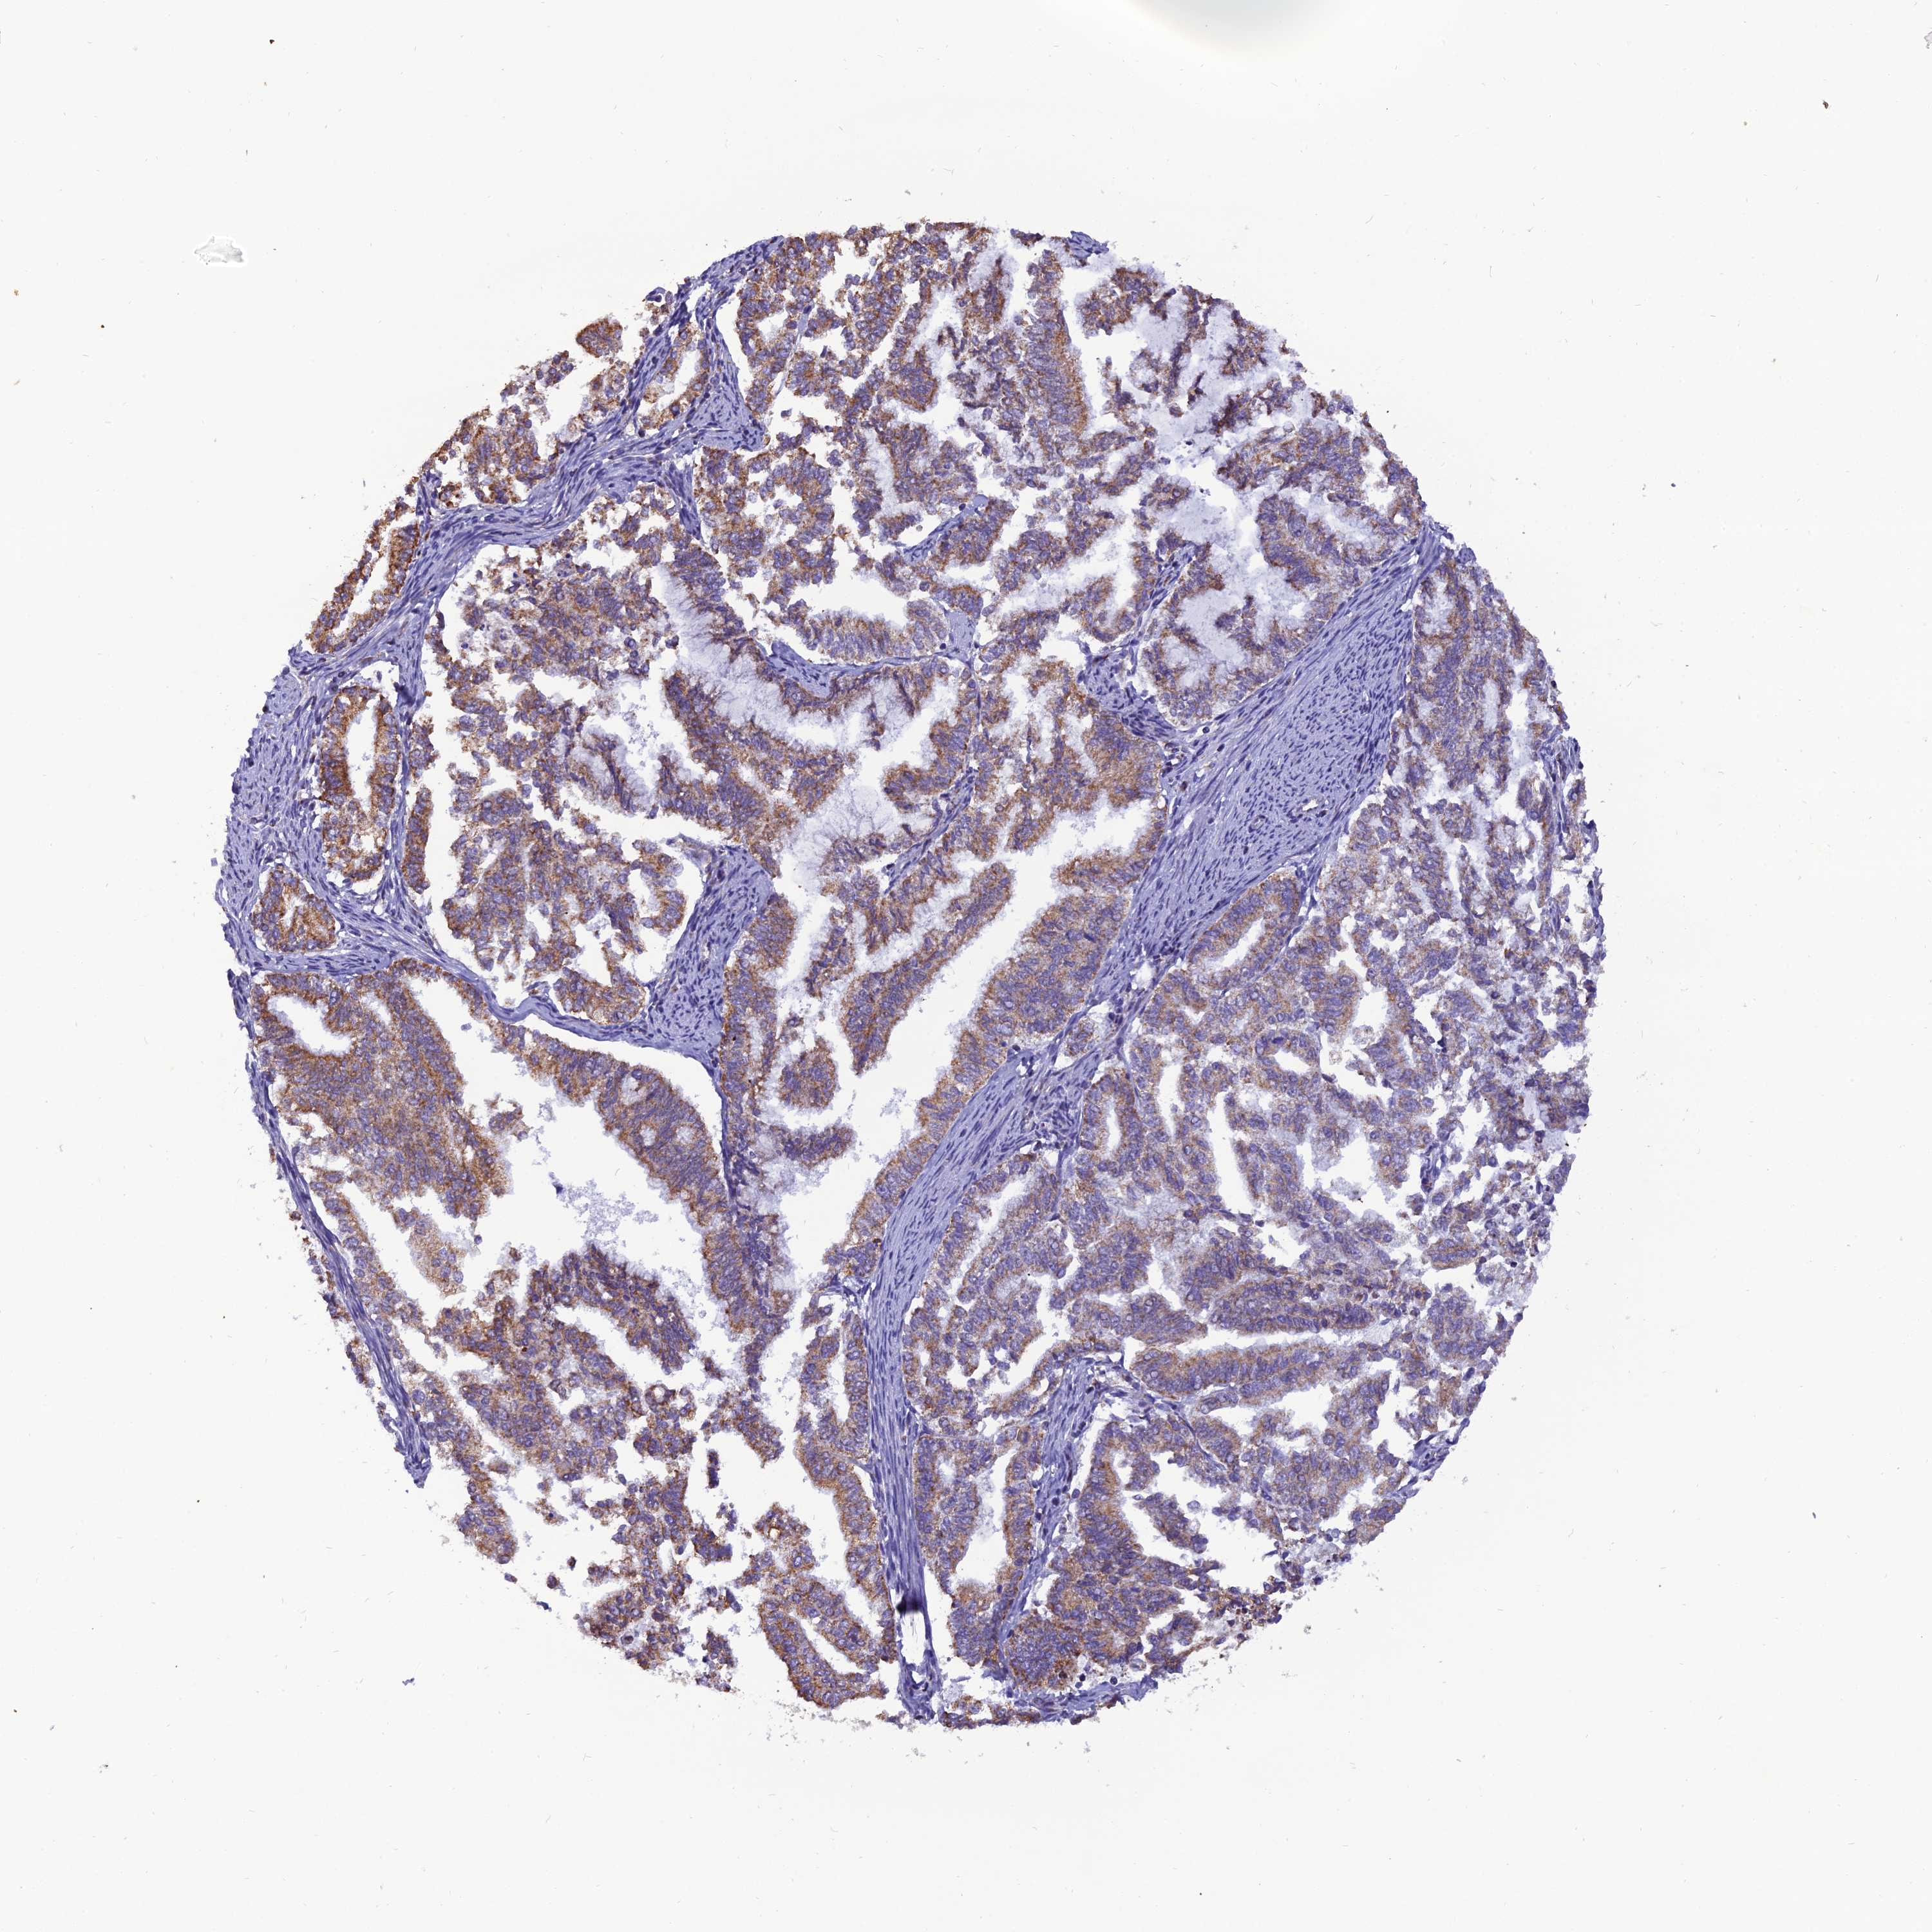

ENDOMETRIAL CANCER - Protein expressioni

A mouse-over function shows sample information and annotation data. Click on an image to view it in a full screen mode. Samples can be filtered based on level of antibody staining by selecting one or several of the following categories: high, medium, low and not detected. The assay and annotation is described here.

Note that samples used for immunohistochemistry by the Human Protein Atlas do not correspond to samples in the TCGA dataset.

Antibody stainingi

Antibody staining in the annotated cell types in the current human tissue is reported as not detected, low, medium, or high, based on conventional immunohistochemistry profiling in selected tissues. This score is based on the combination of the staining intensity and fraction of stained cells.

Each image is clickable and will lead to virtual microscopy that enables deeper exploration of all samples and also displays staining intensity scores, fraction scores and subcellular localization as well as patient and tissue information for each sample.

Antibody HPA044620

Antibody HPA058621

Staining

High

Medium

Low

Not detected

Intensity

Strong

Moderate

Weak

Negative

Quantity

>75%

75%-25%

<25%

None

Location

Nuclear

Cytoplasmic/membranous

Cytoplasmic/membranous,nuclear

Adenocarcinoma, NOS